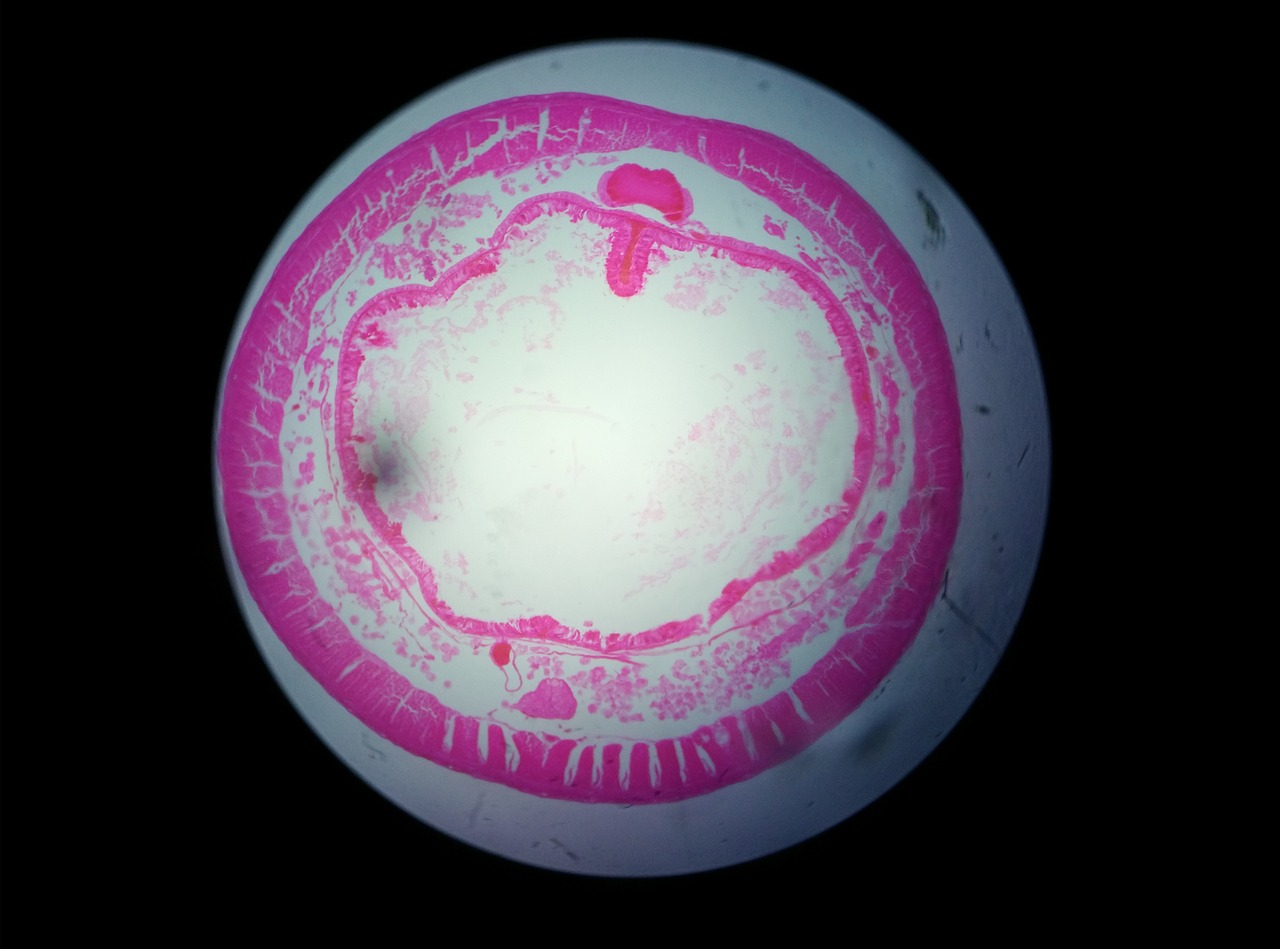

Al término del curso, el alumno conocerá la estructura y funcionamiento

del tejido orgánico humano y sus niveles de organización.